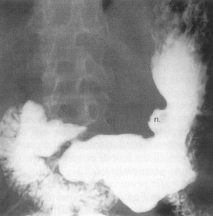

Semnele directe Nisa - imagine de plus de substanta de contrast, corespunzatoare escavatiei peretelui gastric. Din profil imaginea iese din conturul ipotetic al stomacului

Are o forma rotund - ovalara si este dispusa, de obicei, perpendicular.Marimea nisei este variabila, De cele mai multe ori, nisa se localizeaza la nivelul micii curburi în vecinatatea unghiului gastric, dar o putem întâlni si la nivelul micii curburi orizontale, a marii curburi, precum si la nivelul fetelor.

În jurul nisei, exista o reactie inflamatorie edematoasa care se vizualizeaza ca o linie lacunara - linia Hampton bine delimitata, având o grosime uniforma (gulerul ulcerului).